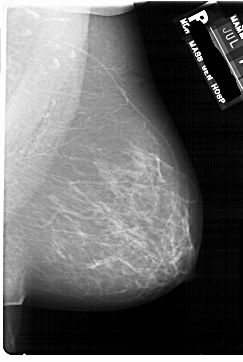

FILE: A_1742_1.LEFT_CC.OVERLAY TOTAL_ABNORMALITIES 1 ABNORMALITY 1 LESION_TYPE MASS SHAPE LOBULATED MARGINS CIRCUMSCRIBED ASSESSMENT 4 SUBTLETY 2 PATHOLOGY BENIGN TOTAL_OUTLINES 1 BOUNDARY |